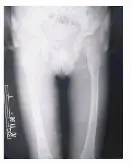

Alteraciones radiológicas: cara y cráneo fontanelas permeables, huesos wormianos con fracturas, hipoplasia malar y mandibular, dientes apiñados; hipoplasia clavicular en el tórax, costillas ahusadas; largos identaciones en los huesos, corticales delgadas, metáfisis anchas, coxa valga, coxa plana, genu valgum; en las falanges acro-osteolisis progresiva de las falanges distales; y otros signos como osteoporosis, escoliosis, cuerpos vertebrales en forma de boca de pescado, luxación de cadera, falta de unión de fracturas y pérdida de tejidos blandos.

3- Rayos X de ambos pies (vista anteroposterior). Osteólisis parcial de falanges distales de ambos pies.

4- Rayos X de pelvis ósea (vista anteroposterior). Coxa valga bilateral.